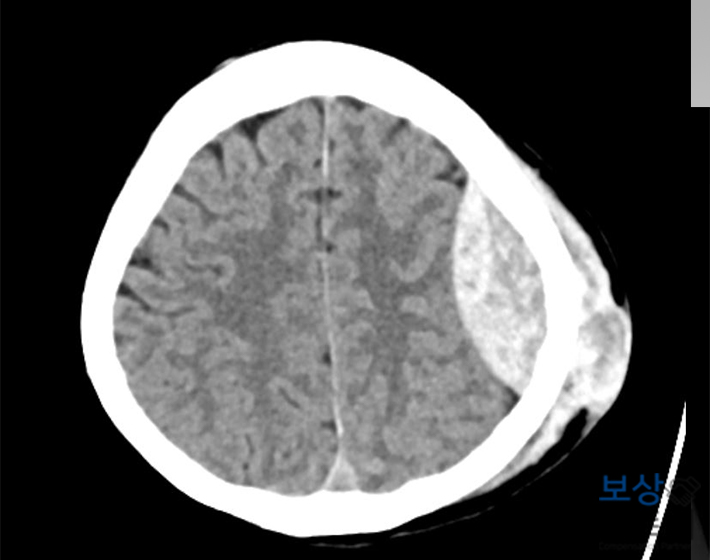

경막외출혈 (S06.4)

좌측 전두엽 부위 외상성 뇌실질내출혈 (S06.3)

좌측 두정골 골절 (S02.0)

두개골 쪽은 두정골 절개술, 혈종 제거술을 받으셨는데요. 경막외출혈 증상으로 인해 뇌가 압박되어서 추후에 후유증이 남을 수도 있는 상황이었습니다. 실제로 회복 과정에서우측 편마비 증상이 나타나셨는데요. 손끝에 힘이 들어가지 않아서 일상생활까지 지장이 가는 상황이었습니다.